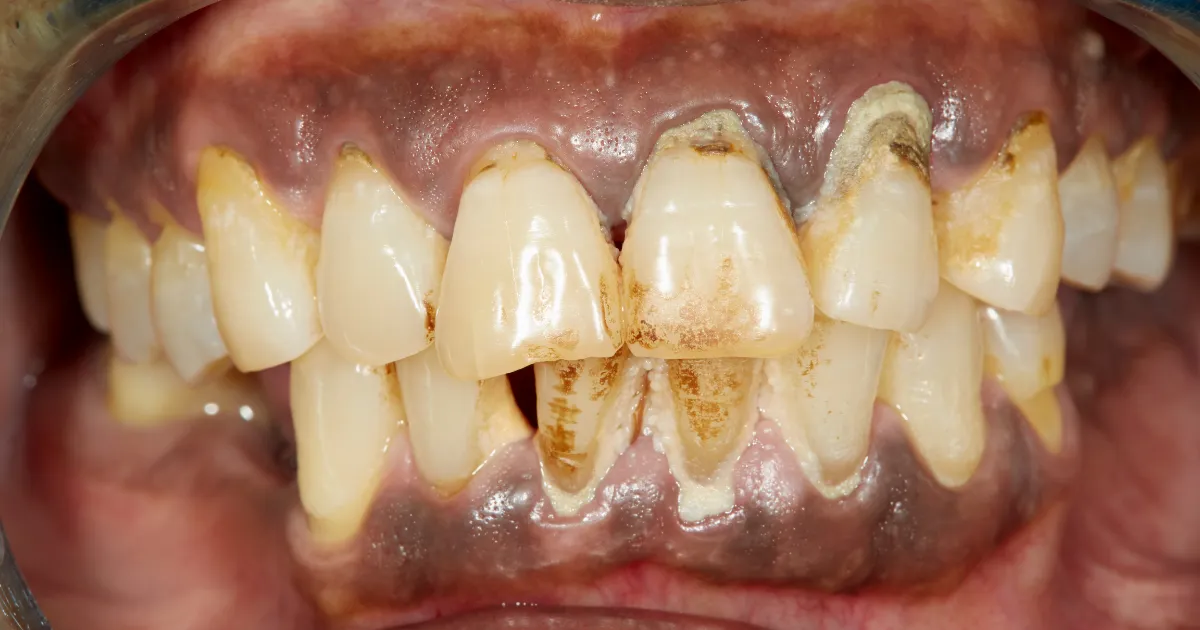

歯周病は、歯と歯茎の間に細菌が入り込むことで炎症が起き、歯茎が腫れたり、出血が見られる病気です。

進行すると歯を支える骨が溶けていき、極端な話歯が抜け落ちるリスクが高まります。

親知らずは、前から数えると8番目で位置的に歯磨きが届きにくく、磨き残しが発生しやすいため、歯周病リスクが高くなります。

また、親知らずが歯茎に部分的に埋まっている場合や、横向きに生えている場合、食べかすや歯垢がたまりやすく、細菌の温床となります。